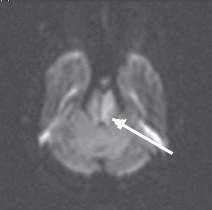

Неинформативность методики ДВИ в определении острого ишемического поражения при локализации в стволе головного мозга можно объяснить двумя факторами. Во-первых, наличием малых ишемических очагов, поскольку перфорирующие артерии васкуляризируют очень маленькие зоны ствола головного мозга. По-видимому, большая часть ложноотрицательных результатов у пациентов с инфарктом ствола головного мозга и незначительным или обратимым неврологическим дефицитом была обусловлена наличием ишемического очага ниже пространственного разрешения изображения (Oppenheim C. et al., 2000; Toi Н. et al., 2003). Во-вторых, нейроны ствола головного мозга (образования более старого в филогенетическом отношении) более стойкие к ишемии, чем нейроны более молодых эволюционно полушарий большого мозга. Это могло быть одной из причин более высокой толерантности их к ишемии и более позднего развития цитотоксического отека ткани ствола головного мозга (Oppenheim C. et al., 2000; Rovira A. et al., 2002; Toi H. et al., 2003). Как известно, ДВИ отображают наличие цитотоксического отека в ишемических очагах ярким сигналом (рис. 4), который соответствует темному сигналу на карте диффузии (рис. 5), обусловленному низким ИКД.

Рис. 4. Острый инфаркт моста головного мозга. ДВИ (аксиальная проекция) через 7 ч после развития заболевания. Гиперинтенсивный (яркий)

МР-сигнал в левой половине моста отображает цитотоксический отек